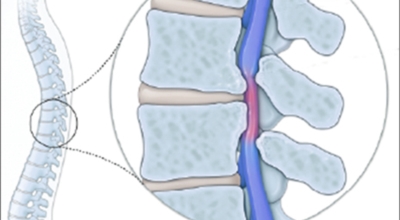

척추관 협착증이란 신경이 지나가는 통로인 척추관이 좁아진 상태를 말하며 척추관 협착증이란 용어는 주로 요추부(허리)에서 사용합니다. 척추관 협착증 환자는 정상에 비해서 척추관이 좁아져 신경이 압박받게 돼요.

협착증은 쉽게 말하여 척추가 나이가 들어서 발생하게 되는 질환으로 척추가 늙게 되면 뼈, 인대, 근육, 디스크. 후관절 등이 약해지며 흔들리게 된다고 합니다. 특히나 디스크의 경우 퇴행이 되면 척추뼈를 잘 잡아주지 못하며 다른 부위인 인대가 잡아주기 위하여 개입을 하게 된다고 합니다. 이렇게 될 경우 신경에 지속적인 자극을 받게 되어 점점 악화되면 정도가 심한 통증을 발생시키게 돼요.